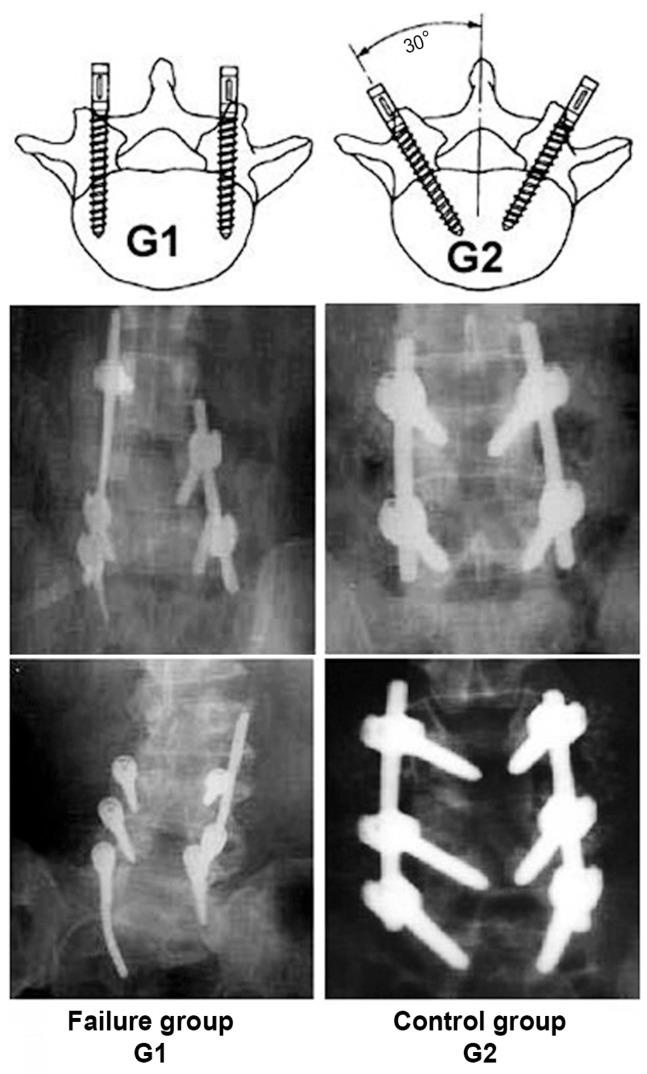

Two hundred patients (88 women, 112 men) were divided into 2 major groups, with 100 patients in group I (implant failure group G1) and 100 patients in group II (successful fusion, control group G2). We subdivided the study groups into two subgroups: subgroup a (single-level instrumented group) and subgroup b (multilevel instrumented group). The implant status was assessed based on intraoperative and follow-up radiographs.

Implant failure in general was present in 36% in G1a, and in 64% in G1b, and types of implant failure included screw fracture (34%), rod fracture (24%), rod loosening (22%), screw loosening (16%), and failure of both rod and screw (4%). Most of the failures (90%) occurred within 6 months after surgery, with no reported cases 1 year postoperatively.